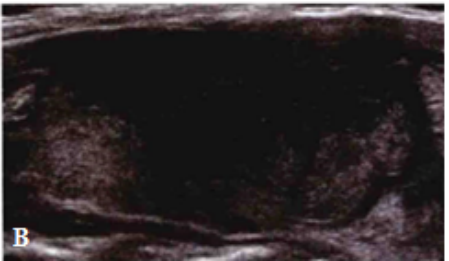

1 型:腺体内散在片状低回声区,或类似无回声区,形态不规则,边界欠清晰,无包膜或声韵,后方无增强效应,也无衰减,其余甲状腺组织回声正常。(见下图)

图源:患者友情提供